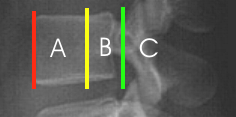

CAVE

- 1) Exakte Aufnahmetechnik? - Projektion korrekt?

- 2) Fehlhaltung z.B. Kyphose (z.B. im Sinne einer traumatischen Kyphose)?

- 3) Beurteilung des Alignments:

- vorderer Wirbelkörperlinie

- hintere Wirbelkörperlinie

- Spinolaminäre Linie

- 4) Physiologische Weichteilbreite

- Höhe A: max. 7 mm

- Höhe B: max. 22 mm

- 5) Physiologische Abstände zwischen Atlasbogen und Dens (C)

- bei Erwachsenen: 2,5 - 3mm (CAVE: Kann bei rheumatoider Arthritis vergrößert sein)

- bei Kindern 3 - 4mm